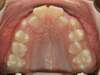

Cas 1 : Description

Après